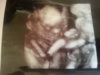

To fotka naszej małej z poniedziałkowego podglądania. Tatuś mówi, że wygląda jak goblin, ale dla mnie to najpiękniejsza buźka na świecie!